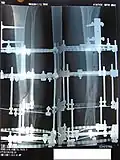

Наложенный аппарат Илизарова

Аппарат изготовляется из специальной нержавеющей стали или титана и состоит из 2 и более колец и 2-3 стяжных стержней, на концы которых навинчены гайка и контргайка. Аппарат стерилизуется; через кость при помощи специальной медицинской дрели проводятся в перекрещивающих направлениях с учётом топографии сосудов и нервов спицы, которые затем фиксируются к кольцам. Перед проведением спицы соответствующие участки кожи смещаются на 0,5–1 см. После проведения спиц на их концы надеваются пропитанные спиртом марлевые салфетки, которые прижимаются пробками. Соединяющие кольца стержни устанавливаются параллельно друг другу. Репозиция обломков костей производится затягиванием гаек и контргаек. Вслед за наложением аппарата осуществляется контрольная рентгенография, позволяющая корригировать положение обломков. Стабильность фиксации поддерживается равномерным подвинчиванием гаек на ¼ оборота каждого стержня до 2 мм каждые 5–7 дней[2].

Процедура лечения открытого перелома большой и малой берцовой костей аппаратом Илизарова. Фотографии и рентгенограммы одного и того же пациента в течение курса лечения. Снимки 2 — 6 сделаны через четыре недели после перелома (две недели после наложения аппарата).